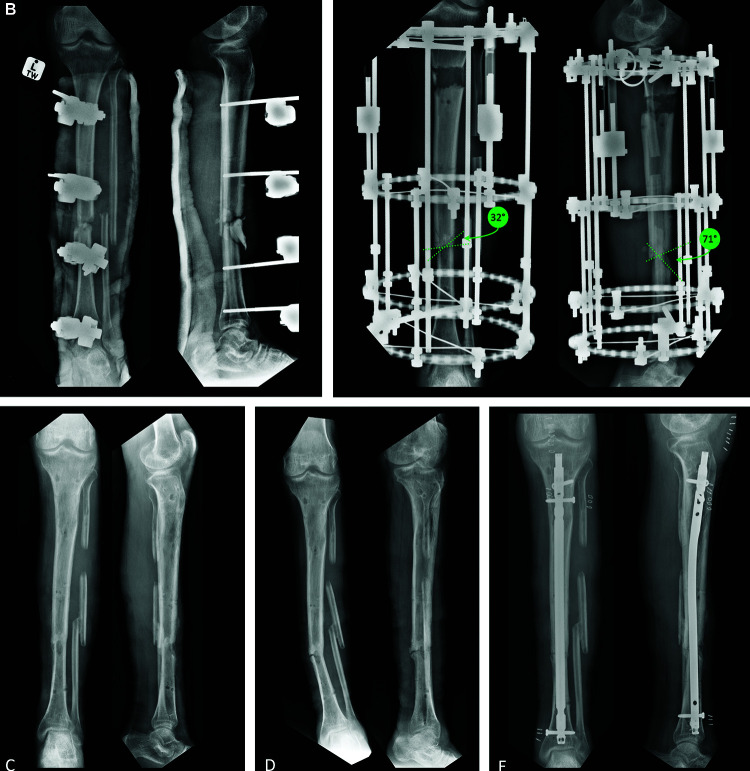

Methods: This retrospective study was conducted at a single tertiary centre in South Africa, included 24 patients with a tibial bone defect treated with bone transport and a circular frame between 2014 and 2023. Demographic data, clinical and bone transport characteristics were recorded. Mechanical complications, such as fracture, non-union, any angulation >5°, shortening >5 mm, or any other complication requiring reoperation, were recorded. The mRUST was adapted as a ratio for the purpose of this study to overcome the common occurrence of cortices being obscured by the frame. The mRUST ratio was applied before and after frame removal for each patient by three appraisers. Comparison between the groups with and without complications was performed regarding bone transport characteristics, docking site configuration and mRUST ratio. The correlation of the score between radiographs before and after frame removal was assessed. The inter-rater reliability of the mRUST was analysed using Fleiss Kappa statistics for each cortex individually and the intraclass correlation coefficient (ICC) for the mRUST ratio.

Results: In this study, 20 men and 4 women with a median age of 26 years were included. The overall rate of mechanical complications after frame removal was 21.7%. Complications were all related to the docking site, with two angulations, two fractures and one non-union. Demographics, bone transport characteristics and mRUST ratio before and after frame removal were similar between the two groups. Regarding the configuration of the docking site, an angle of 45° or more between the bone surfaces was associated with the occurrence of mechanical complications (p < 0.001). The correlation of the mean mRUST ratio before and after frame removal showed a moderate relationship, with a Spearman correlation coefficient of 0.50 (p-value 0.13). The inter-rater reliability of the mRUST was "fair" (kappa 0.21-0.40) for the scoring of individual cortices, except for one score which was "slight" (kappa 0.00-0.20). The ICC of the mRUST ratio was 0.662 on radiographs with the frame, and 0.759 after frame removal.

Conclusion: This study did not find the mRUST or mRUST ratio useful in assessing the healing of the docking site to decide on the best time to remove the frame. However, a notable finding was that the shape and orientation of the bone ends meeting at the docking site might well be relevant to decrease complication rates. If the angle between the bony surfaces is 45° or more, it may be associated with an increased risk of complications. It may be worthwhile considering reshaping these bone ends at the time of debridement or formal docking procedure to be more collinear, in order to reduce the potential for mechanical complications such as non-union, axial deviation or refracture at the docking site.